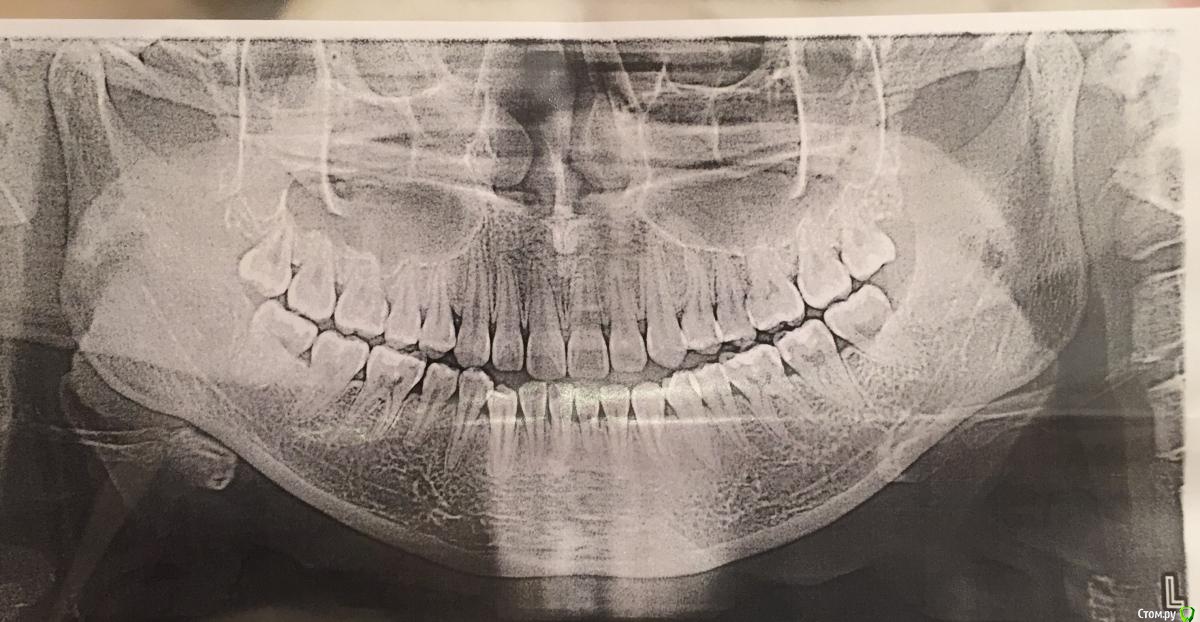

Помогите разобраться, мнения коллег разошлись.

Пациентке 21год, беспокоит 43 выдвинут вперёд, рецессия Десны у 14, 24.

1. Поставить брекеты, чтоб выровнять нижний ряд.

2. Удалить 48 и 28 и затем поставить брекеты

3. Ничего не делать, оставить так как есть.

когда удалять 8-ки -  решает ортодонт, как ему удобнее будет, каким образом он будет использовать это пространство (если никак, то в любое время, если будут пружины, MEAW,  то возможно ему удобнее будет в середине удалить... это он решает)

а вариант номер 3 - это уже на усмотрение пациента, надо ему это или нет